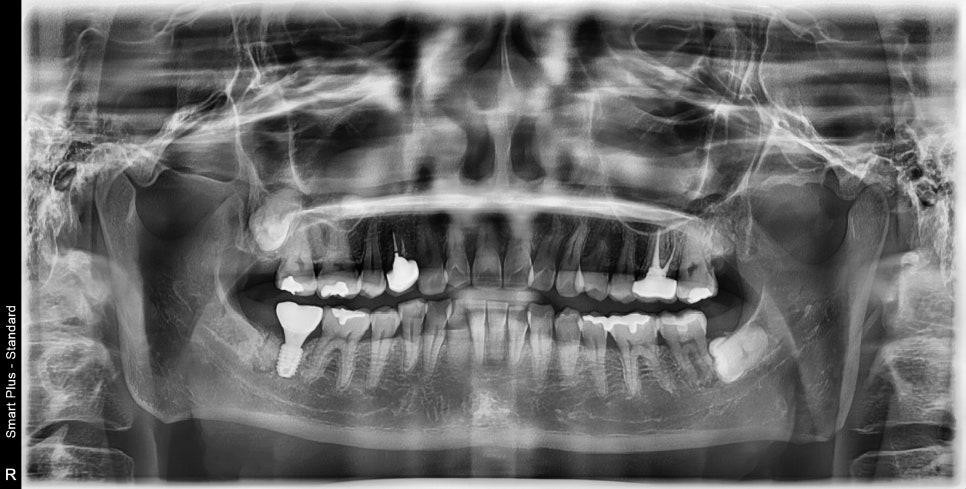

타치과에서 오른쪽 아래 어금니 발치 진단을 받으셨습니다.

과거에 잠시 통증이 있었지만 현재는 증상은 없지만

치아 주변 뼈가 많이 소실된 것을 볼 수 있습니다.

CT를 찍으면 더 확실하게 볼 수 있습니다.

뿌리 주변의 검은색으로 보이는 곳들이 염증으로 인한 치조골이 소실된 것입니다.

방사선 사진상에서도 뿌리에 금이 갔을 때 보이는

전형적인 치조골 소실 양상입니다.